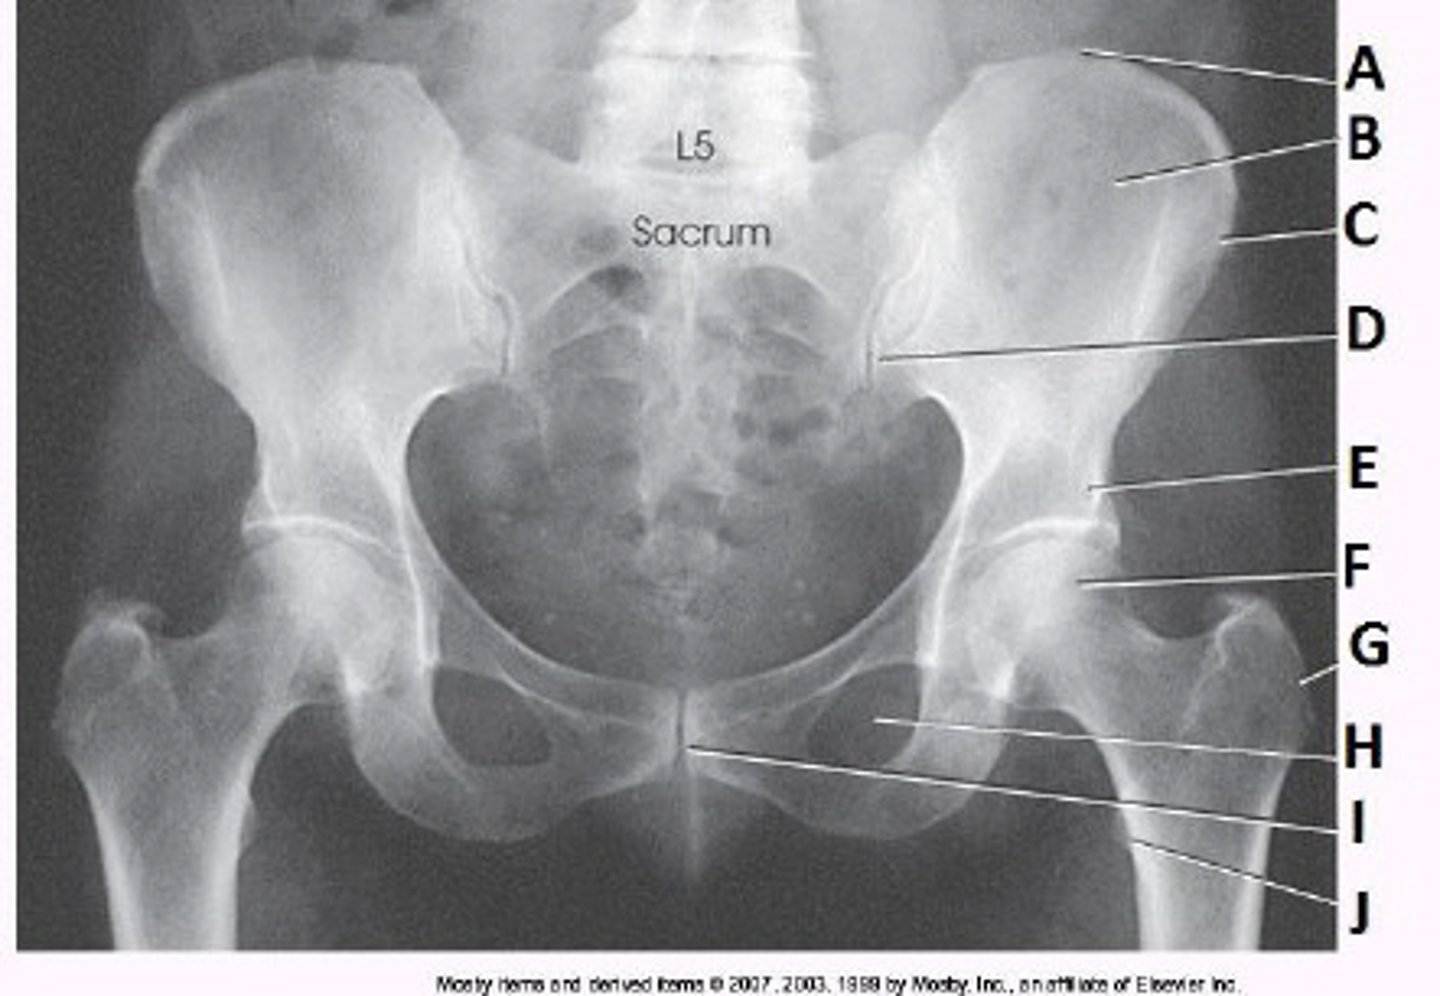

What positioning error is evident in the image below?

The lower limbs were not internally rotated

The part identified on the ilium above is the _____ iliac spine.

anterior superior

What anatomy is labeled as letter C in the image below?

ASIS

What anatomy is labeled as letter B in the image below?

Lesser trochanter

What anatomy is labeled as letter A in the image below?

Acetabulum

Identify the projection:

AP Pelvis

Identify the anatomy marked A:

Ischial tuberosity

The anatomy marked with #6 is the:

Ischial spine

Identify the anatomy marked with #7:

Pubic bone

Is this pelvis rotated?

Yes

The anatomy marked with #3 is the:

Greater trochanter